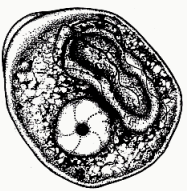

Blastocystis hominis (cyst)

Blastocystis hominis